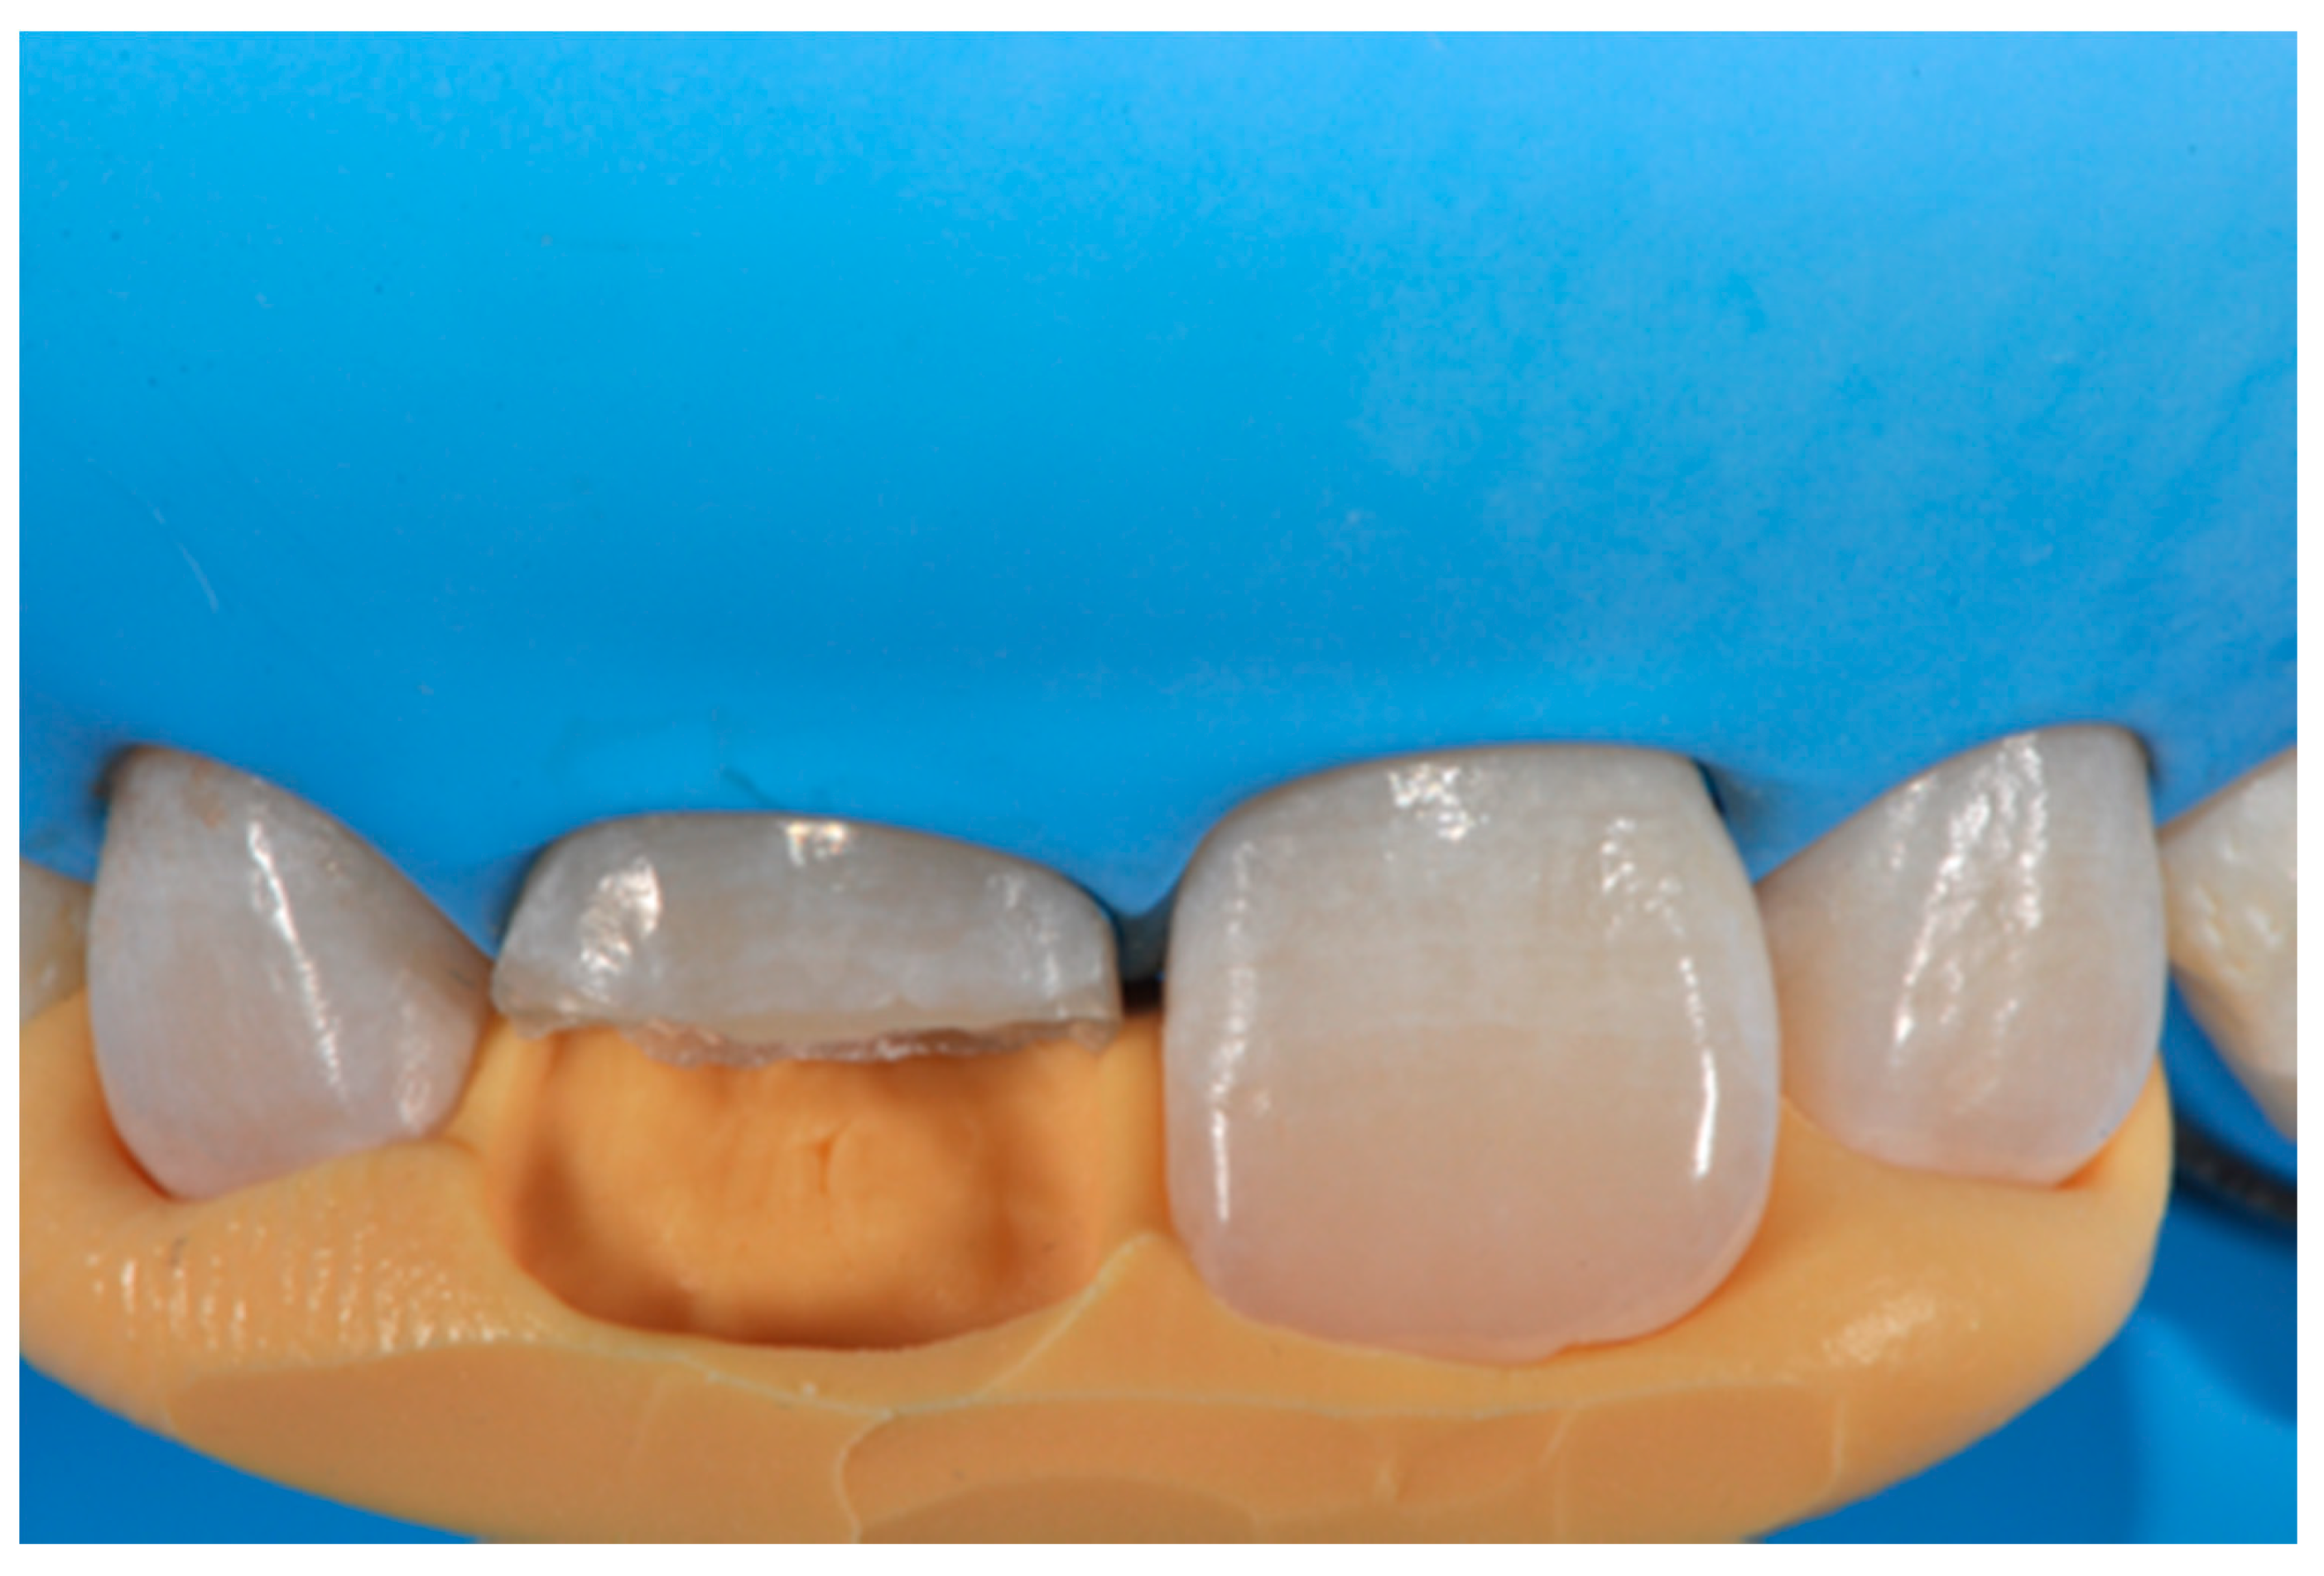

Once completed, the two frames (Clearfil Majesty ES-2, A1E, A2D, Kuraray Noritake Dental, Tokyo, Japan) showed internal and external excesses that were reduced using diamond burs and discs (Figure 33 and Figure 34) strictly following the procedure described in Section 2.1.2 of present article. Excesses were removed from the distal-incisal angle of #2.1 allowing therefore to obtain the desired translucency. After silane application and bonding procedure (Figure 35) as described in Section 2.1.2, restorations were completed (Figure 36 and Figure 37). They both show satisfactory clinical integration 1.5 years post-operative (Figure 38 and Figure 39).

Figure 33.

Frame imprecisions are corrected by reducing interproximal wall from the internal side. Reprinted from Restauri diretti nei settori anteriori, G. Paolone, S. Scolavino, © 2021, with permission from Quintessence Publishing Italy.

Figure 34.

Frame is also trimmed reducing external outline. Reprinted from Restauri diretti nei settori anteriori, G. Paolone, S. Scolavino, © 2021, with permission from Quintessence Publishing Italy.

Figure 35.

The modified frames treated with silane coupling agent and adhesive, ready for layering of dentinal body. Reprinted from Restauri diretti nei settori anteriori, G. Paolone, S. Scolavino, © 2021, with permission from Quintessence Publishing Italy.